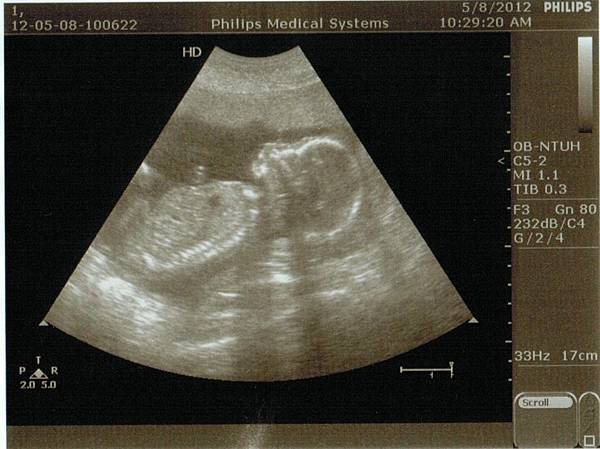

Desmond, 18週3天大。

最近這一陣子,喜事、鳥事、有的沒有的事一堆,腦子裡想的東西一多,相對地就對肚子裡的這一個老二想的少。一直到今天醫生超音波儀器在我肚皮上移阿移的,我在電腦螢幕上清楚地看到這小子揮動的小手臂跟雙腳、清晰可見的脊椎,還有雙腳間跟當初哥哥第一次被照到就清晰可見尖尖小凸起,突然間我才有 -- "Wow! This is for real!" 的感覺。

那小凸起相當地明顯,明顯到D在醫生說出『是小男生喔!』之前就搶先一步說 "It looks like we're having a boy agian!",當下我第一個反應是忍不住地嘆了口氣(Desmond, 媽媽不是故意的),然後被D狠狠地瞪了一眼。唉呦~嘆氣是因為Desmond的中文名、小名媽媽我都還沒想好阿!